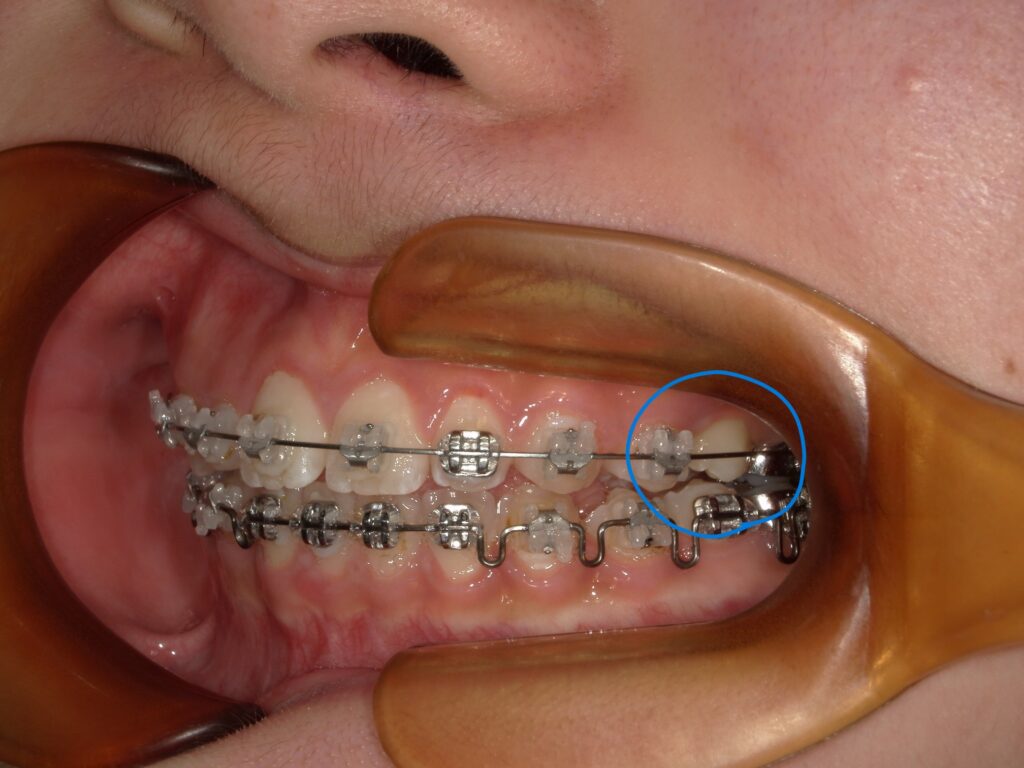

【原因2】歯の形や位置の影響

ブラケットは歯の表面に接着しますが、歯の形状によっては接着面積が少なく、外れやすくなる場合があります。特に以下のようなケースは要注意:

- 犬歯や小臼歯など、表面が丸みを帯びた歯

- 噛み合わせによって、ブラケットが常に他の歯に当たっている位置